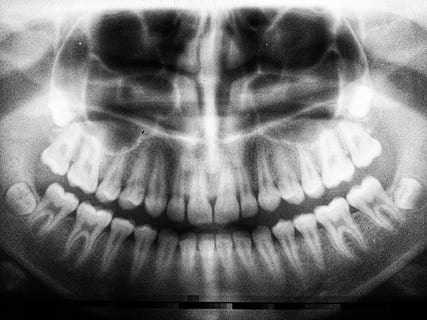

royalty free hand x-ray photos free download - PiqselsLos pacientes ciertamente están expuestos a rayos X de diagnóstico dental, y los odontólogos también pueden recibir exposición. Aunque el nivel de exposición es más bajo que el de la radiación médica, existe un riesgo innato de la exposición a la radiación que no se puede ignorar. Sin embargo, hay algunos estudios sobre la exposición a rayos X de diagnóstico dental en dosis bajas y los efectos sobre la salud, excepto con respecto a algunas partes del cuerpo. Además, los artículos informan significados estadísticos inconsistentes sobre la exposición a rayos X de diagnóstico dental y los efectos sobre la salud, según los sujetos y el diseño de la investigación; por lo tanto, los estudios relacionados deben organizarse sistemáticamente. Por lo tanto, a través de una revisión sistemática de la literatura, este estudio incluyó varios estudios con diferentes diseños de investigación y examinó los riesgos para la salud asociados con la exposición a rayos X de diagnóstico dental. Para la revisión de la literatura, este estudio examinó veintiún artículos sobre la exposición a rayos X de diagnóstico dental y los efectos sobre la salud.

Entre veintiún artículos que informaron una correlación entre las radiografías de diagnóstico dental y la salud general, dieciocho artículos evaluaron una correlación con las áreas de la cabeza y el cuello. Los artículos seleccionados incluyeron diez sobre cáncer de cerebro, cinco sobre cáncer de tiroides y tres sobre áreas de la cabeza y el cuello distintas del cerebro y la tiroides. Dado que la cavidad oral se encuentra anatómicamente cerca de la cabeza y el cuello [36], los exámenes de rayos X dentales parecen afectar las áreas del cerebro y el cuello. La correlación de los rayos X con los cánceres de cerebro y de tiroides se ha informado durante muchas décadas y parece explicar este hallazgo.

Los tipos de rayos X de diagnóstico dental se clasificaron específicamente. Especialmente, los tipos de exámenes panorámicos se usan con más frecuencia que los tipos simples de rayos X dentales, porque la cobertura de información de diagnóstico panorámico supera la de los rayos X de diagnóstico dental. Los exámenes panorámicos también requieren menos pasos que los tipos de examen de boca completa convencionales. El tipo de boca completa tuvo una correlación estadística con el meningioma y los cánceres de glándulas salivales. El cáncer de meningioma mostró un riesgo cuatro veces mayor a edades más jóvenes (20 años). A diferencia de los adultos, los niños son mucho más sensibles a la exposición a la radiación debido a la división celular activa. Además, el tipo de examen panorámico mostró una correlación con el cáncer de meningioma a frecuencias de exposición más altas. En consecuencia, se necesita un estudio sobre la cantidad de exposición a la radiación de cada tipo de rayos X de diagnóstico dental. No obstante, los artículos seleccionados sobre el cáncer de tiroides, que tiene un alto nivel de sensibilidad a la radiación, no categorizaron los tipos de rayos X de diagnóstico dental, por lo que no se pudo examinar.